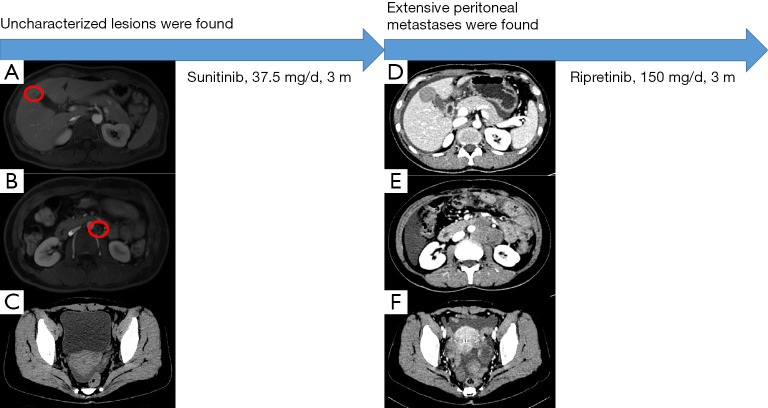

鑒于腫瘤對伊馬替尼有耐藥性,患者在手術(shù)后口服舒尼替尼(37.5 毫克/天)。 患者狀態(tài)良好,未發(fā)生藥物不良反應(yīng)。 2021 年 1 月的腹部 CT 掃描未見明顯異常。 2021年5月腹部磁共振復(fù)查示肝右前葉異常信號,較2021年1月結(jié)果新,考慮血管瘤可能性大(見圖2A)。 此外,在腹主動脈左側(cè)觀察到淋巴結(jié)腫大(見圖 2B),還有少量盆腔積液(見圖 2C)。

圖 2

案例第 2 階段的圖形摘要。 (A) 無法識別的肝臟微觀病變(由紅色圓圈顯示)。 (B) 腹主動脈旁的小淋巴結(jié)(紅色圓圈所示)。 (C) 少量盆腔積液。 (D) 肝轉(zhuǎn)移。 (E) 主動脈旁轉(zhuǎn)移。 (F) 盆腔腹水和轉(zhuǎn)移性結(jié)節(jié)。

患者2021年8月的腹部CT顯示腹部和骨盆多處軟組織結(jié)節(jié)和腫塊,與2021年5月的結(jié)果相比是新的,考慮轉(zhuǎn)移。 腫瘤基因解碼醫(yī)師還注意到肝臟右前葉的低密度病灶比以前更大,并考慮轉(zhuǎn)移(見圖2D)。 此外,在腹主動脈周圍觀察到多個腫大的淋巴結(jié),并考慮轉(zhuǎn)移(見圖2E),并且還觀察到腹部盆腔積液(見圖2F)。 鑒于患者腫瘤的基因突變類型,患者從三線 TKI 瑞戈非尼中獲益的可能性很小,因此患者接受了口服利培替尼(150 mg/天)治療。 2021年10月,患者繼續(xù)服藥,狀態(tài)良好但有輕微腹脹。 她將如期接受審查。